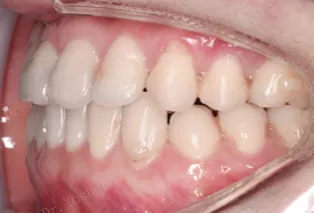

Photos intra-orales